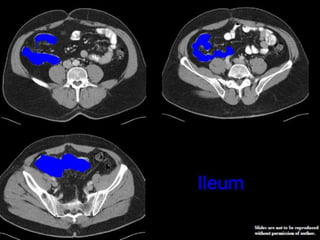

CT cross sectional anatomy.